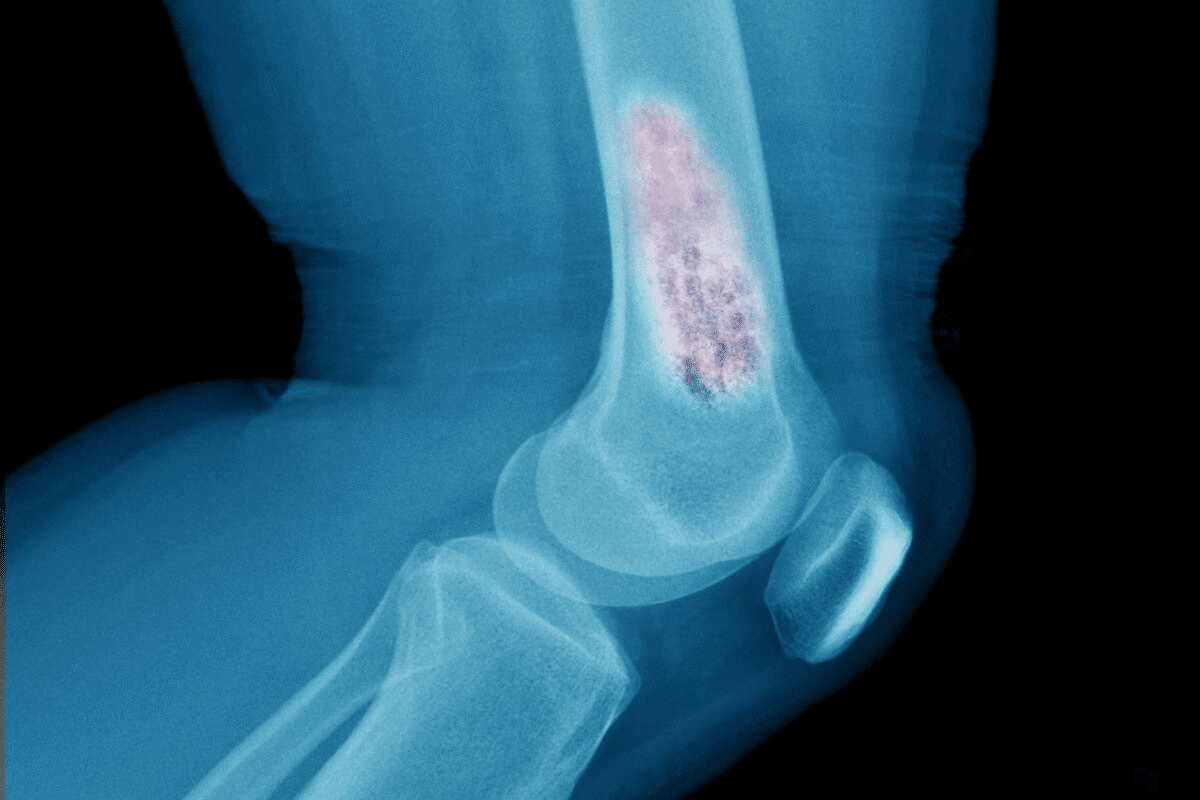

Bone density tests are key for checking osteoporosis risk. But, many wonder if they can find cancer. These tests, or DEXA scans, mainly look at bone mineral density to spot osteoporosis or predict fracture risk.

DEXA scans use low-dose X-rays to determine bone density. They give useful info on bone health. Yet, they can’t spot cancerous tumors or lesions well.

DEXA scans can’t find cancer because they’re not detailed enough. They’re made to measure bone density, not see tumors. They show bone density in grams per square centimeter (g/cm²) and give scores to show bone health.

DEXA scans are for bone density, not for finding tumors. They’re made to see bone, not soft tissue like tumors. So, they can’t give the detailed images needed for cancer diagnosis.

Even though DEXA scans aren’t for cancer, they can sometimes find things that worry you. Like vertebral fractures or odd bone loss. If this happens, you might need more tests like X-rays or MRIs to figure out what’s going on.

X-rays are the first test used when bone cancer is suspected. They show bone structure abnormalities, like lesions or fractures. But, X-rays can’t see soft tissue involvement or early bone density changes well.